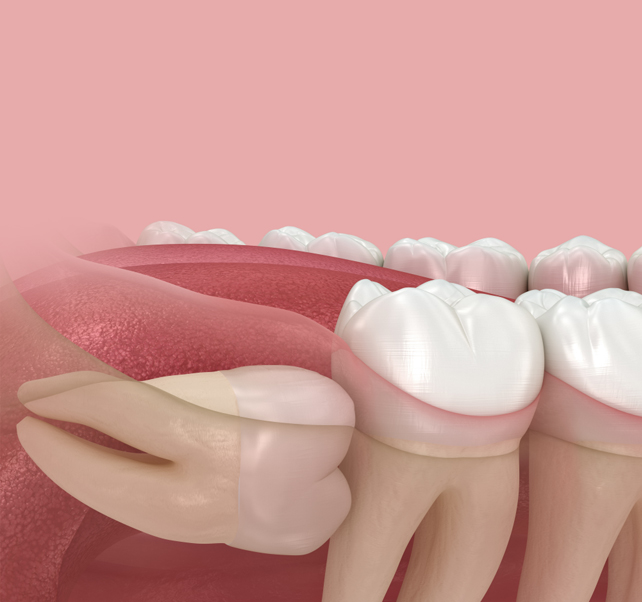

사랑니 발치 PROCESS

05

하루만에 발치 후 바로 식립하는발치즉시 임플란트

발치한 당일에 임플란트 식립을 진행하기 때문에

내원 횟수를 줄여 불편함을 최소화하고 치료 기간도 단축시킬 수 있습니다.

다만, 모든 분들이 가능한 것은 아니기 때문에 정밀 진단 후

숙련된 의료진과의 상담이 필요합니다.